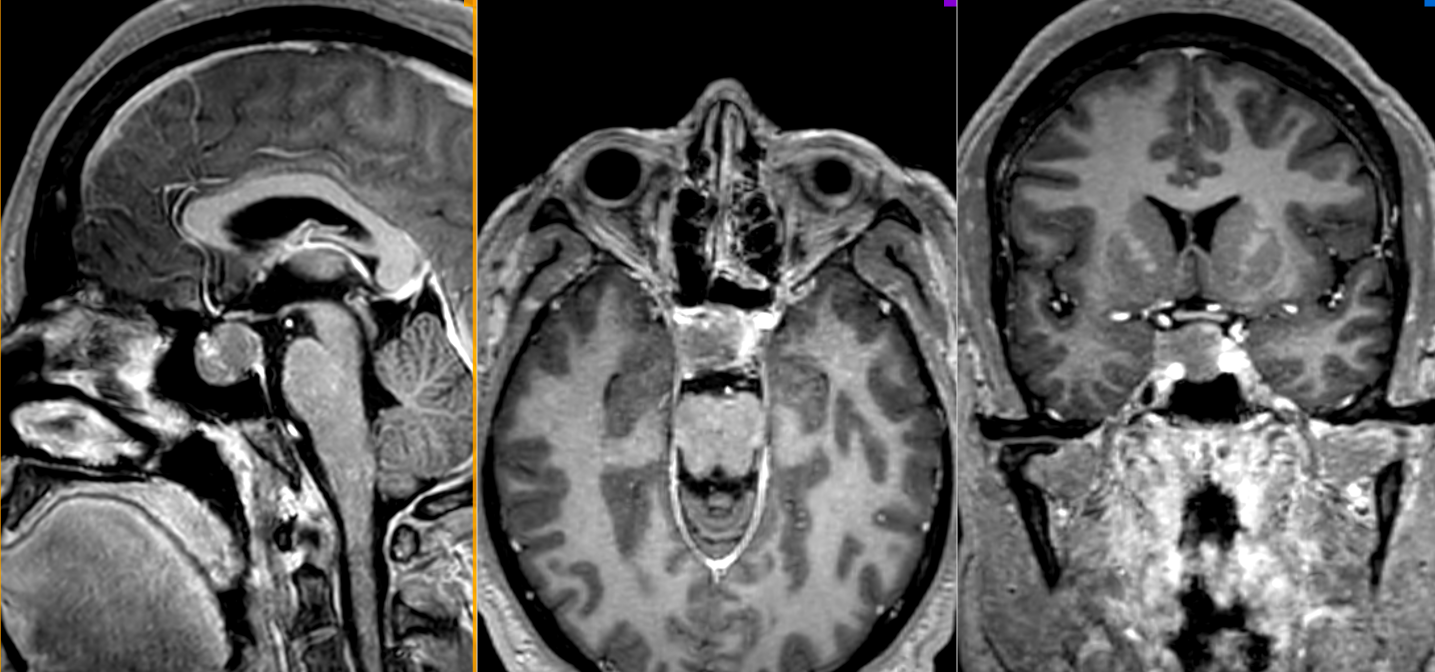

- RMN cerebral cu contrast este metoda de elecție pentru vizualizarea tumorii.

- Macroadenoamele hipofizare apar ca mase tumorale cu priza de contrast localizate la nivelul șeii turcești, eventual cu extensie superioară (supraselară) spre nervii optici sau, mai rar, inferioară, în sinusul sfenoid; de multe ori ele se pot extinde și lateral, în sinusurile cavernoase (structuri vasculare venoase formate în grosimea meningelui care mărginește lateral șaua turcească, prin care trec arterele carotide interne).

- Microadenoamele necesită un tip special de examinare RMN, cu secvențe repetate (în dinamică) realizate după administrarea substanței de contrast. Ele apar de obicei ca niște defecte de umplere – mici zone ne-gadolinofile (glanda hipofiză normală capteaza contrast mai repede decât adenomul); alteori singurul indiciu despre existența și localizarea adenomului (în afară de analizele hormonale) îl constituie asimetria glandei cu devierea tijei hipofizre de partea opusă